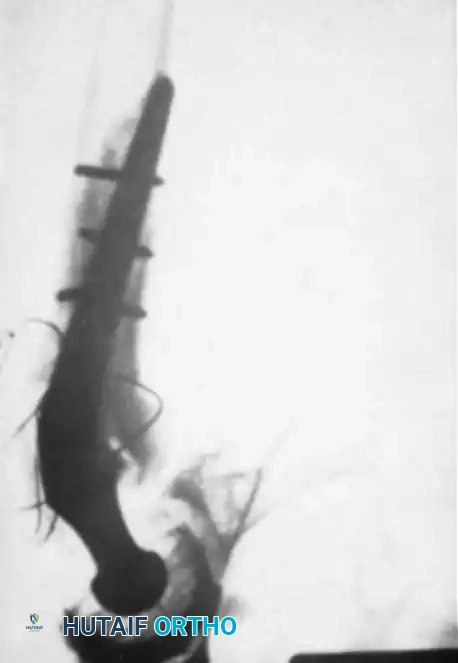

Arthrodesis with Hip Compression Screw Fixation

Pagnano and Cabanela popularized the use of a sliding hip compression screw (dynamic hip screw) supplemented by cancellous screws. This construct offers several distinct advantages:

1. It ensures the hip is fused in the proper position, minimizing low back pain.

2. It provides dynamic compression across the fusion site, promoting primary bone healing.

3. It avoids bulky hardware that might damage the abductor muscles, preserving them for future THA.

4. It minimizes the need for postoperative spica casting.

Technique Overview:

Following standard joint denudation, the hip is positioned optimally. A guide wire is passed from the lateral proximal femur, through the femoral neck, and deep into the thickest portion of the ilium (above the acetabular dome). The tract is reamed, and a large lag screw is inserted. A side plate is applied to the lateral femur, and compression is achieved. Two or three additional cancellous screws are placed proximal to the hip screw to provide rotational stability.

Final construct showing the dynamic hip screw and supplementary anti-rotation cancellous screws.

Postoperative Protocol: Patients are evaluated at 12 to 14 weeks. If stable union is questionable, a removable polypropylene orthosis is used for another 4 to 6 weeks. Full recovery often takes 6 months. Routine removal of the hardware is advisable after 18 months to promote bone remodeling and facilitate future conversion to THA.